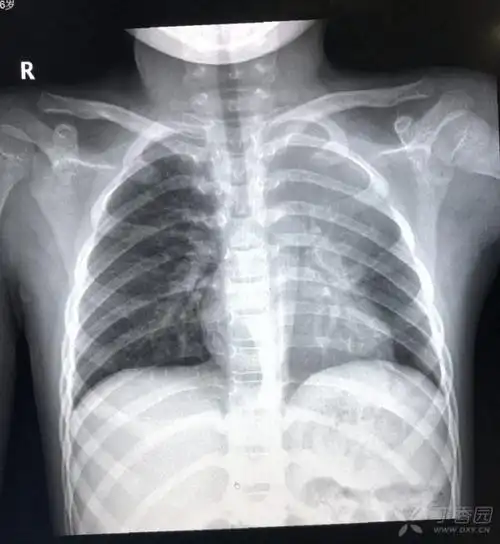

双胞胎反复肺炎的原因,及下一步处理. [病例帖]